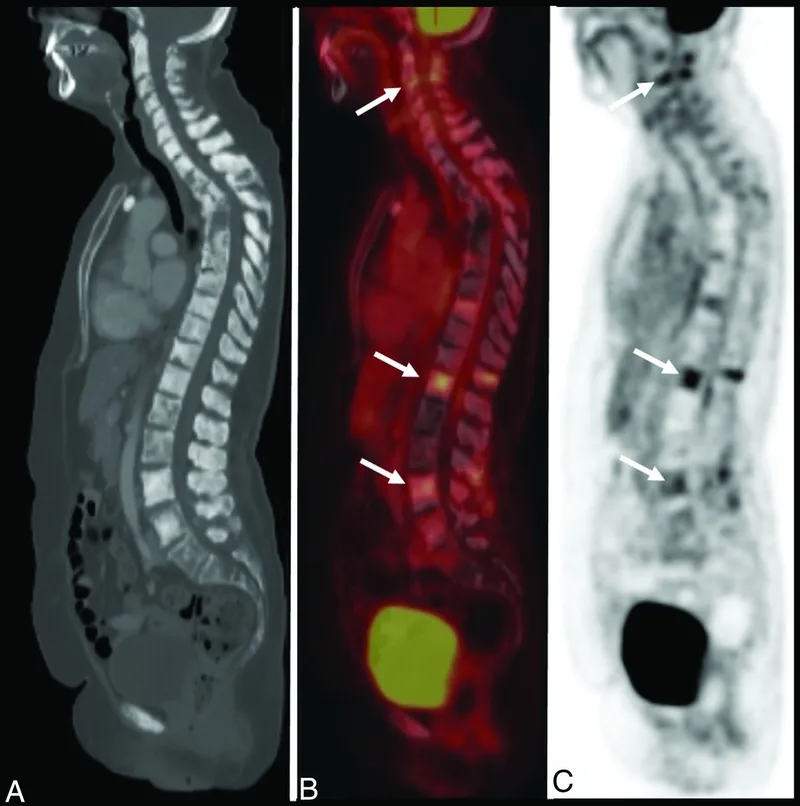

- PET-CT: Whole-body staging, assessing metabolic activity, and treatment response.

- MRI: Best for marrow infiltration, soft tissue extension, spinal cord assessment (especially for compression).

- X-ray: Initial; may show lytic (lucent), blastic (sclerotic), or mixed lesions; periosteal reaction.

- Bone Scan (Tc-99m MDP): Detects ↑osteoblastic activity / bone turnover (hot spots).